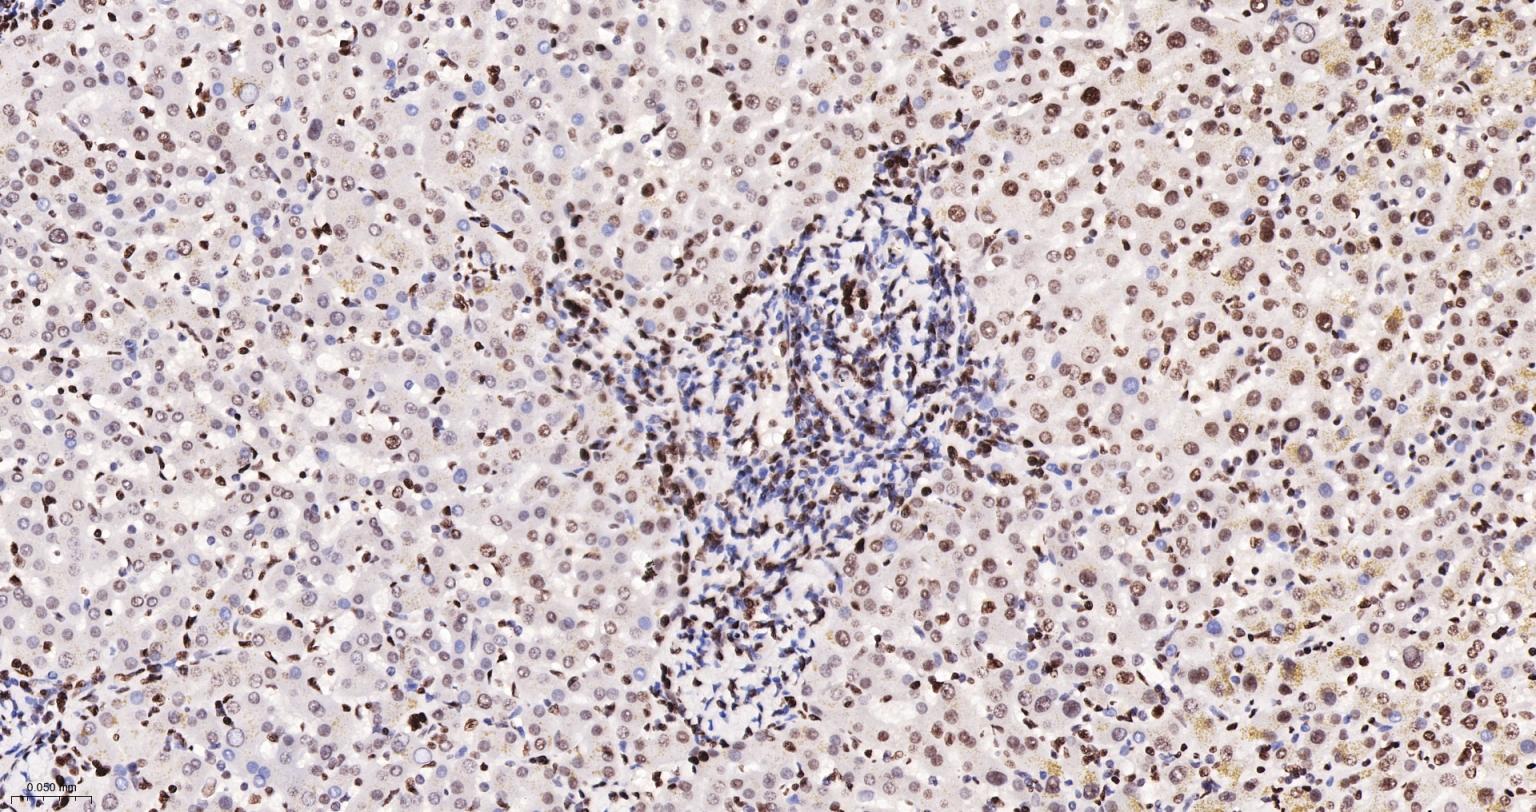

Paraformaldehyde-fixed, paraffin embedded Human Liver; Antigen retrieval by boiling in sodium citrate buffer (pH6.0) for 15 min; The section was incubated with Acetyl-Histone H3(K9) Monoclonal Antibody, Unconjugated (bsm-63244R) at 1:200 overnight at 4°C, followed by conjugation to the bs-0295G-HRP and DAB (C-0010) staining.

Paraformaldehyde-fixed, paraffin embedded Rat Liver; Antigen retrieval by boiling in sodium citrate buffer (pH6.0) for 15 min; The section was incubated with Acetyl-Histone H3(K9) Monoclonal Antibody, Unconjugated (bsm-63244R) at 1:200 overnight at 4°C, followed by conjugation to the bs-0295G-HRP and DAB (C-0010) staining.

Paraformaldehyde-fixed, paraffin embedded Mouse Liver; Antigen retrieval by boiling in sodium citrate buffer (pH6.0) for 15 min; The section was incubated with Acetyl-Histone H3(K9) Monoclonal Antibody, Unconjugated (bsm-63244R) at 1:200 overnight at 4°C, followed by conjugation to the bs-0295G-HRP and DAB (C-0010) staining.